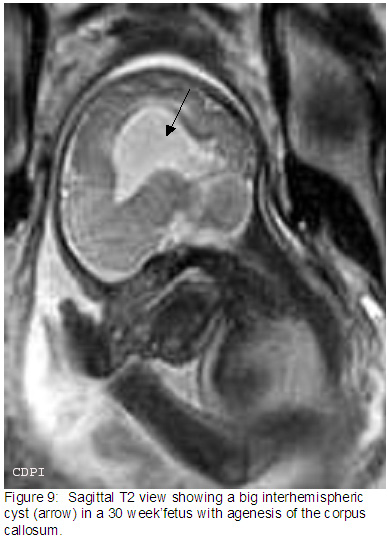

9. На саг.Т2 большая межполушарная киста (стрелка) у 30 недельного плода с агенезией мозолистого тела.